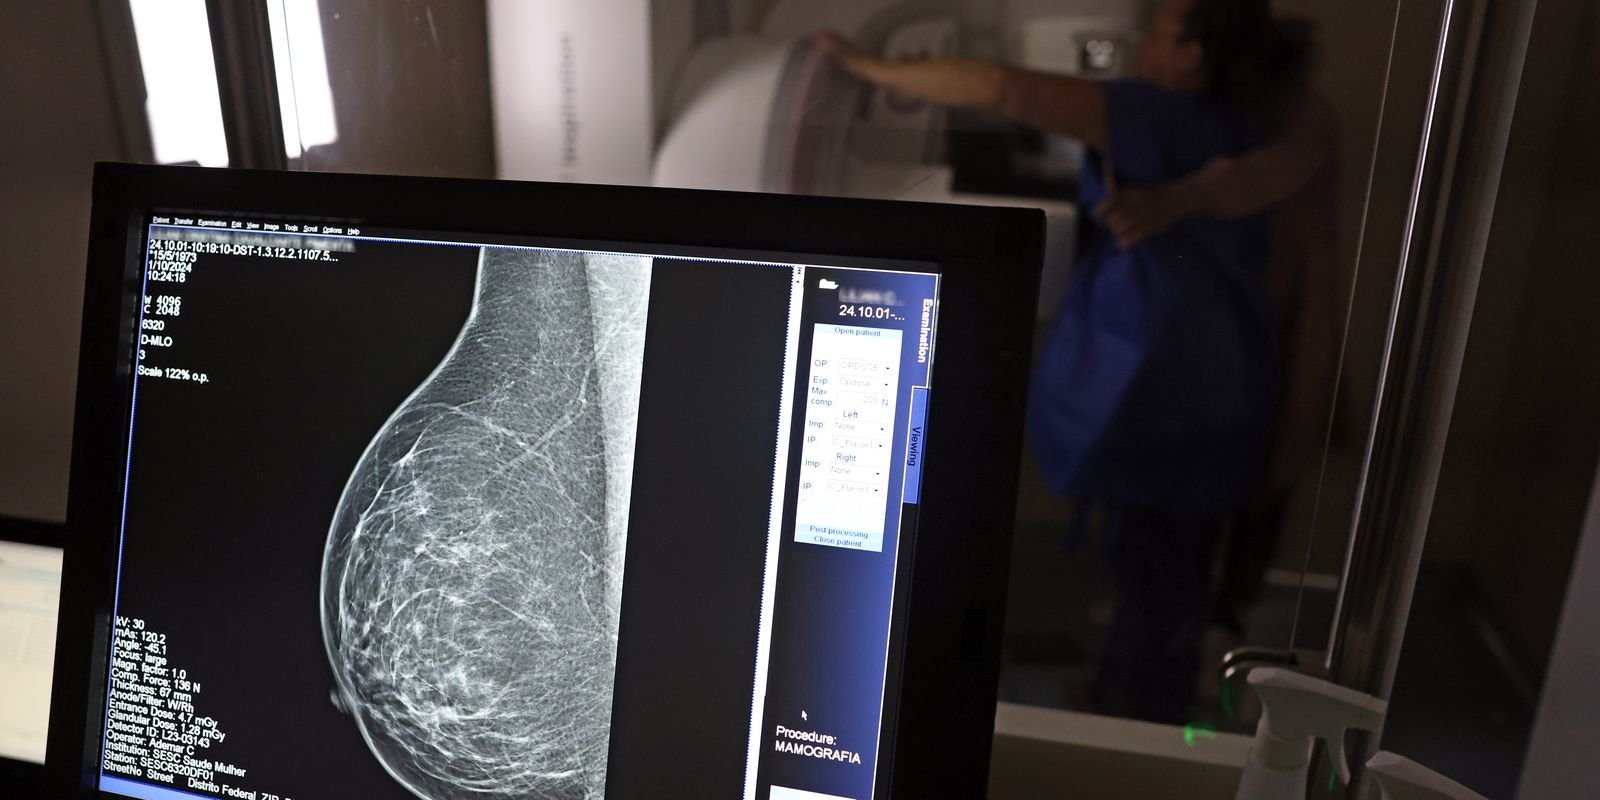

No Outubro Rosa, o Instituto Nacional de Câncer (Inca) estimou 73.610 novos casos este ano no país. É o câncer que mais mata mulheres no Brasil. As mulheres em tratamento pela doença têm o direito de receber o auxílio-doença ou o benefício de prestação continuada.

A vice-presidente da Comissão de Previdência Social Pública da Ordem dos Advogados do Brasil do Rio de Janeiro (OAB-RJ), Danielle Guimarães, destaca que o câncer de mama é uma das doenças que mais afetam mulheres no Brasil, impactando não apenas a saúde física e emocional, mas também a capacidade de trabalho e a segurança financeira das pacientes.